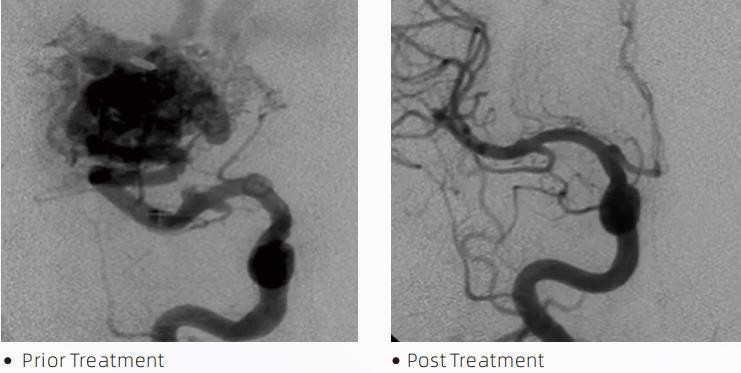

Lub LavaTMLiquid Embolic System yog ib txoj kev kho mob endovascular rau kev kho mob cerebrovascular malformations. Cerebrovascular malformation yog hais txog ib pawg ntawm benign lossis malignant neurovascular abnormalities uas tuaj yeem ua rau intracranial hemorrhage, cerebral infarction, cerebral ischemia thiab lwm yam kab mob. Cov kua embolization system yog cov cuab yeej kho mob uas tswj hwm los ntawm kev yooj yim intravascular insertion, uas embolizes cerebral hlab ntsha txawv txav los ntawm kev txhaj tshuaj tshwj xeeb ntawm cov kua dej. Cov kua dej tsim cov ntaub so ntswg embolism hauv cov hlab ntsha, uas tuaj yeem txo qhov cuam tshuam ntawm cerebrovascular malformations rau cov neeg mob. Ib qho DMSO tau tshaj tus me nyuam micro catheter uas tau qhia rau kev siv hauv neurovasculature yog siv los nkag mus rau qhov chaw embolization. Lava kua embolic tus neeg sawv cev yog ib qho uas tsis yog-adhesive kua embolic tus neeg sawv cev system muaj EVOH (ethylene vinyl cawv) copolymer yaj hauv DMSO (dimethyl sulfoxide), thiab tshem tawm micronized tantalum hmoov los muab qhov sib piv rau kev pom hauv qab fluoroscopy. LavaTMmuaj nyob rau hauv peb cov khoom formulations, LAVA-12, LAVA-18 thiab LAVA-34. LAVA-12: Pom zoo thaum pub mis rau cov hlab ntsha hauv nruab nrab thiab los ntawm cov khoom me me. LAVA-18: Pom zoo thaum noj tshuaj pedicle yuav tsum tau ua nyob ze rau nidus; LAVA-34: Pom zoo rau embolizing ntau dua flow thiab loj fistulous Cheebtsam.